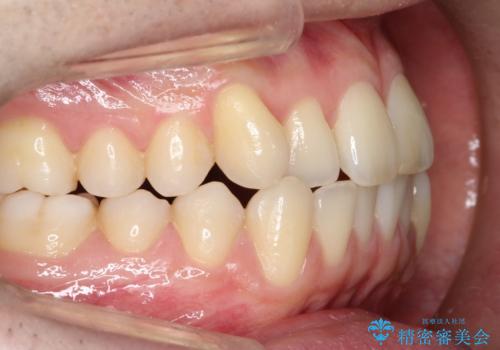

【クリア装置】前歯の凸凹を綺麗にしたい

- 前歯の凸凹を主訴に来院されました。

マウスピース矯正も適応でしたが、ワイヤー矯正を希望され治療を行なっております

治療期間も短く大変満足していただきました。